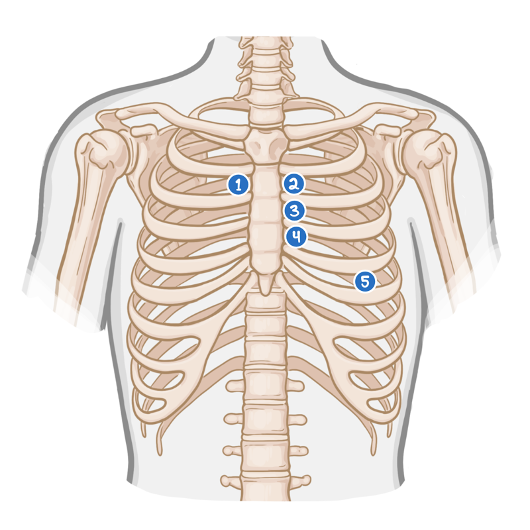

A 75-year-old man presented with an episode of syncope two days ago. The patient was working in his garden when he suddenly felt light-headed and lost consciousness for one minute. The patient endorses worsening shortness of breath and occasional chest pain during his usual morning walk for the past month. His temperature is 36.0°C (96.8°F), pulse is 75/min, and blood pressure is 138/87 mmHg. On physical examination, the lungs are clear to auscultation. Neurologic examination is normal. ECG: LVH. Cardiac auscultation will most likely reveal a murmur in which of the areas marked on the diagram below?

- Area 1: Crescendo-decrescendo systolic murmur.

- Area 4: Holosystolic murmur.

- Area 3: Systolic ejection murmur.

- Area 5: Opening snap followed by diastolic murmur.

- Area 2: Ejection murmur accompanied by a fixed split-second heart sound (S2).